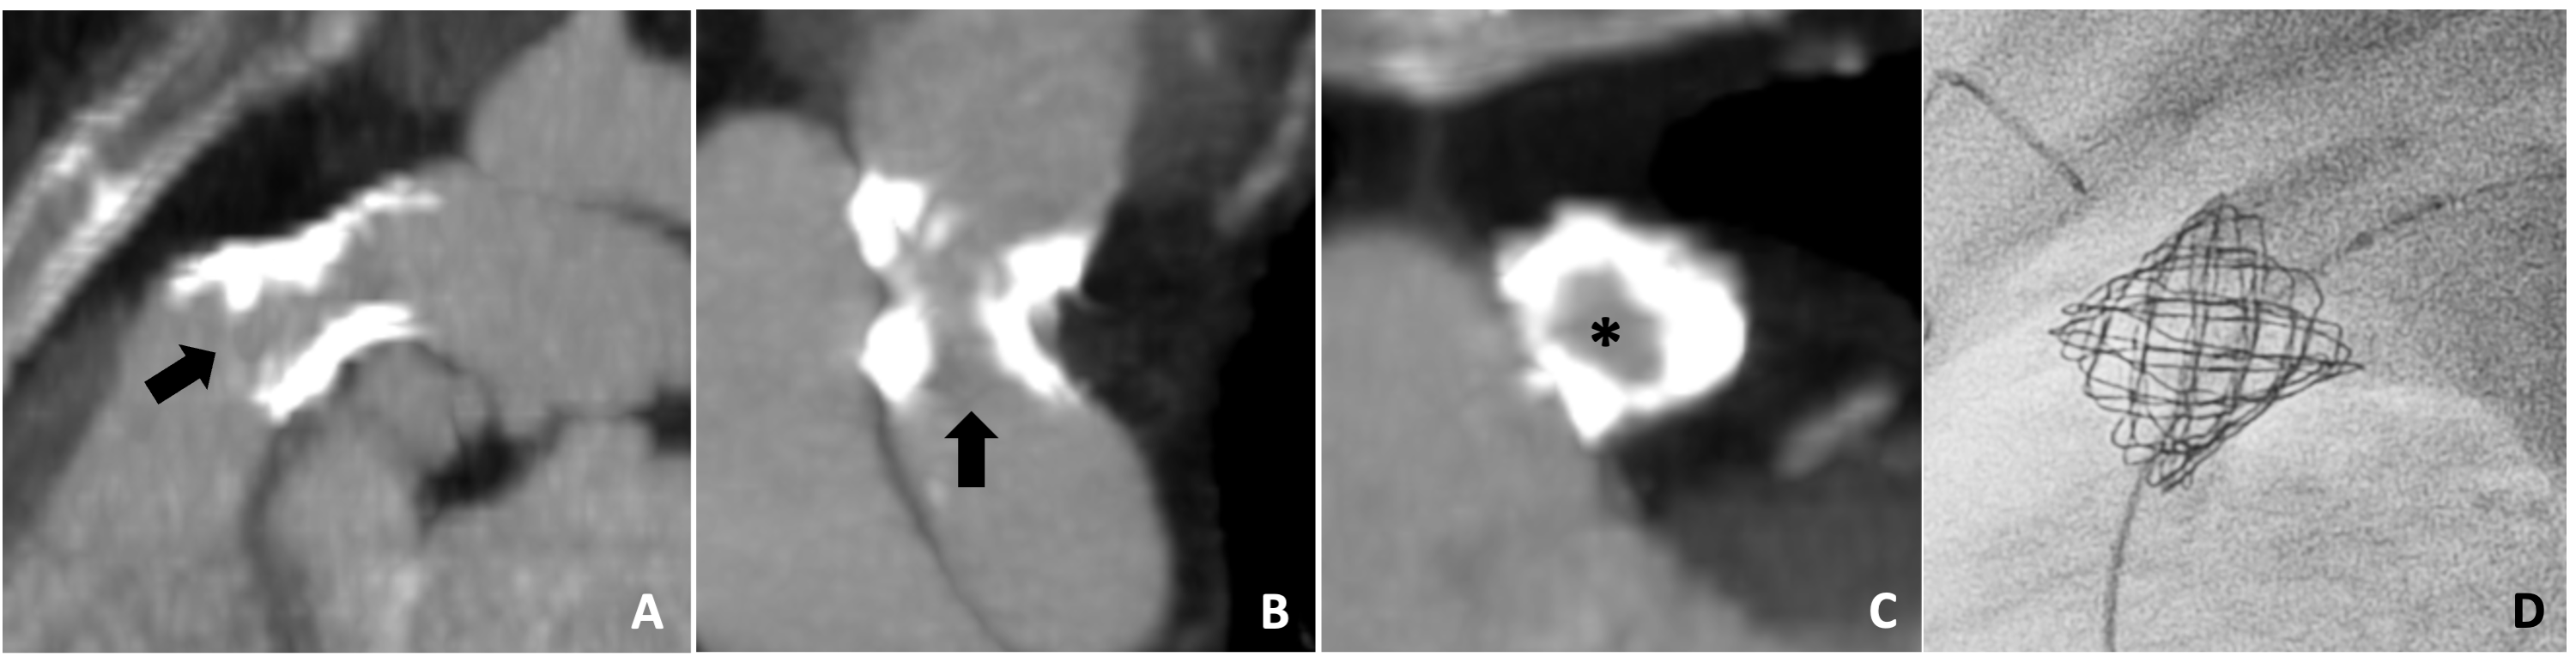

A 25-year-old man with a history of D-transposition of the great arteries who underwent staged palliation culminating in an arterial switch procedure with a LeCompte maneuver by 1 month of age, followed by 2 subsequent surgical aortic valve replacements (AVR). During the second AVR, he required branch pulmonary artery (PA) reconstruction with homograft material as a result of longstanding bilateral branch PA stenoses. In the setting of progressive bilateral branch PA stenoses, he was brought forward for branch PA stenting. A pre-procedural cardiac computed tomographic angiogram (CTA) revealed severe bilateral ostial PA stenoses measuring 4 x 5 mm and 8 x 15 mm within the right and left PAs with distal reference diameters of 11 x 13 mm and 21 x 25 mm, respectively. Heavy circumferential right PA calcification was present, presumed to be homograft tissue from the prior repair (Figure 1A-C).

The procedure was carried out with bilateral venous access and simultaneous wiring of the branch PAs. Initial angioplasty of the right PA origin with an 8-mm Charger balloon (Boston Scientific) inflated to 10 atm without alleviation of a mid-balloon waist. Attempts to place a covered stent prior to a more aggressive angioplasty were unsuccessful because of an inability to deliver a long 12-French sheath across the heavily calcified lesion. As such, the decision was made to perform IVL to the ostial right PA. A 0.014-inch exchange length guide wire was advanced into the distal right PA and a 7-mm Shockwave IVL balloon was advanced over the wire and into the right PA. The balloon was inflated to 4 atm and a total of 60 lithotripsy pulses were delivered, resulting in near complete relief of the mid-balloon waist, suggesting adequate lithotripsy (Figure 1D and E). Following IVL, 2 covered Cheatham-Platinum stents (CCPS) (Numed Inc.) and a Palmaz 4010 XL stent (Cordis) were implanted and post-dilated with a 12-mm balloon to 30 atm, resulting in a substantial improvement in the right PA caliber to a minimum diameter of 10 mm. Left PA stenting was performed without difficulty, resulting in substantial reduction in the right ventricular systolic pressures and a decrease in the right PA gradient from 55 to 15 mm Hg. There were no periprocedural complications and the patient was discharged within 24 hours. A CTA performed several months later demonstrated widely patent branch PA stents (Figure 1F).